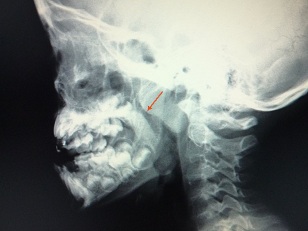

睡眠時無呼吸症候群かきうち耳鼻咽喉科クリニック。

アデノイド肥大 - 春日井市の坂井耳鼻咽喉科。